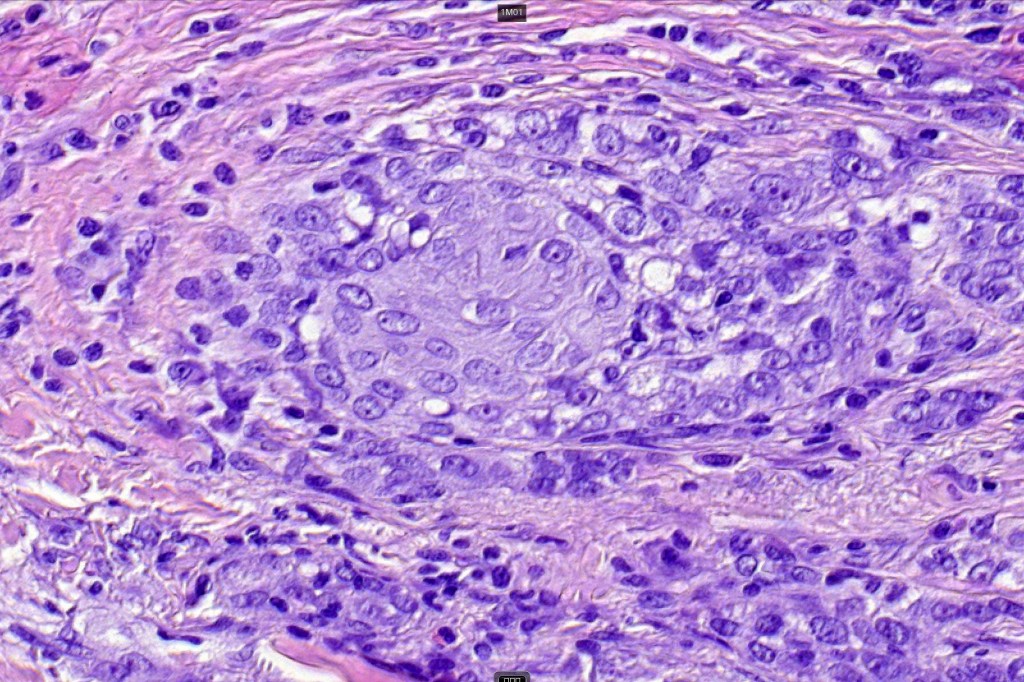

•Biphasic tumor combining squamous cell carcinoma and adenocarcinoma; the latter showing ductal and glandular differentiation

•Glands are lined by cuboidal to columnar epithelium

•Intracytoplasmic lumina sometimes evident

•Glandular foci show mucin